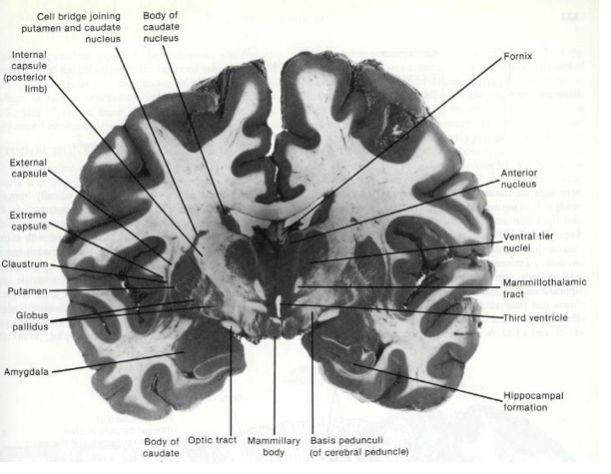

Fill in the blank.

Fill in the blank

What makes up the lentiform nucleus?

putamen

globus pallidus

What makes up the corpus striatum?

caudate nucelus and lentiform nucleus

What seperates the lentiform nucleus from the caudate nucleus?

internal capsule

Where is the substantia nigra?

in the midbrain